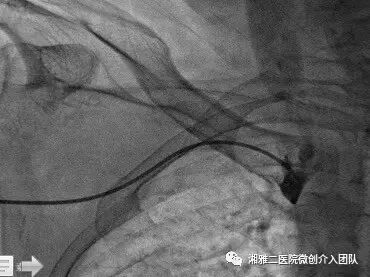

肿胀手手术的穿刺需要使用超声,以上为超声引导穿刺过程图像

穿刺成功后行顺行性造影,了解狭窄的部位和程度

使用高压注射器造影